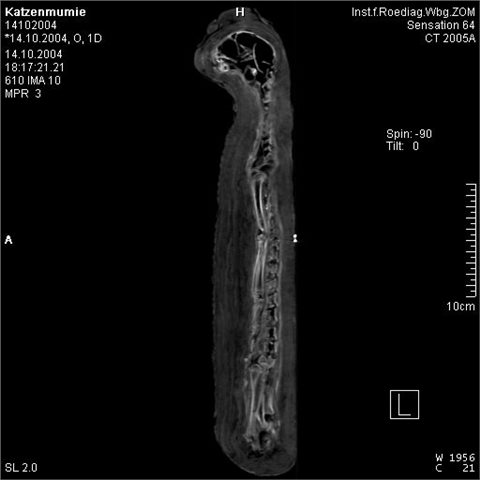

CT-Aufnahme der Katzenmumie.

Wie radiologische Untersuchungen an zahlreichen Katzenmumien in ägyptischen Sammlungen ergaben, enthalten Katzenmumienbündel oftmals tatsächlich gar keine mumifizierte Katze, sondern nur vereinzelte Knochen, teilweise sogar nur Lehm und Steine. Andererseits sind auch Katzenmumien, die aus den Skeletten von bis zu sechs Einzeltieren bestehen, bekannt.

Die zoologische Zuordnung zu den in Altägypten belegten beiden Spezies Felis chaus (Wildkatze) und Felis silvestris libyca (domestizierte Katze) ist sehr schwierig, da hierfür meist nur die Knochen sehr jung getöteter Tiere zur Verfügung stehen.